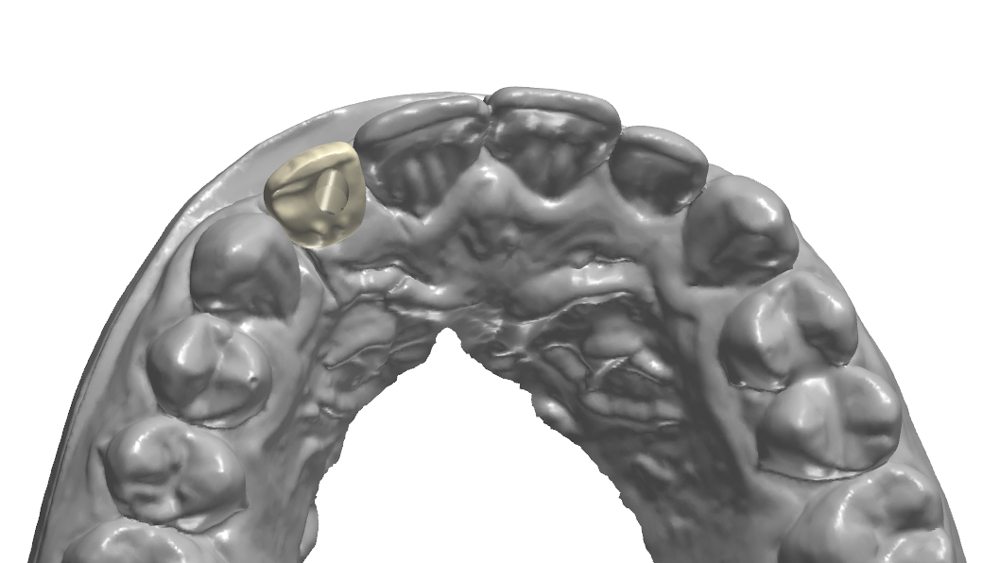

The Hahn Guided Surgical Kit (Glidewell Direct) has been designed to eliminate the need for drill keys, inserts or “spoons” commonly found in other guided surgery systems. The surgical kit’s efficient, straightforward sequence of drills creates an osteotomy in the exact shape, diameter and length of the prescribed implant, ensuring the implant ends up in the exact position determined by the digital treatment plan. Further, the entire surgical procedure, from the initial osteotomy to implant placement, is performed through the surgical guide. Whether using the Digital Treatment Planning service of Glidewell Laboratories or another source for surgical guides, specific guide sleeves are provided to enable practitioners to perform the entire surgical procedure with an efficient and fully guided protocol.

The following case illustrates the efficient, straightforward clinical workflow for placing Hahn Tapered Implants via guided surgery. A digital treatment plan is developed in which a 3.5 mm implant is positioned to support the ideal prosthetic outcome. An immediate provisional crown is designed in concert with the surgical guide and delivered at the time of surgery, helping to produce a predictable, highly esthetic restoration for a demanding case in the smile zone.